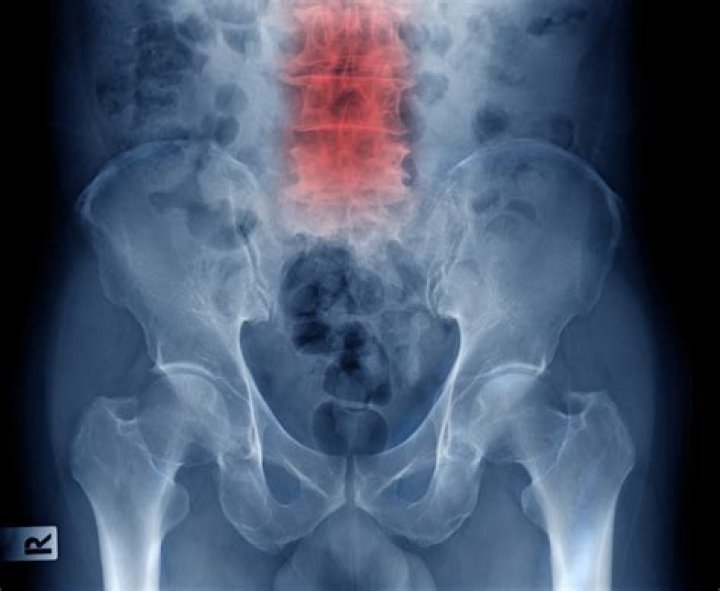

When is spondylolisthesis serious

To see if your spondylolisthesis is unstable and moving, the doctor may perform flexion and extension views from the side. These are also called lateral bending views. A flexion x-ray is taken with you bending forward; an extension x-ray is taken with you bending backwards.